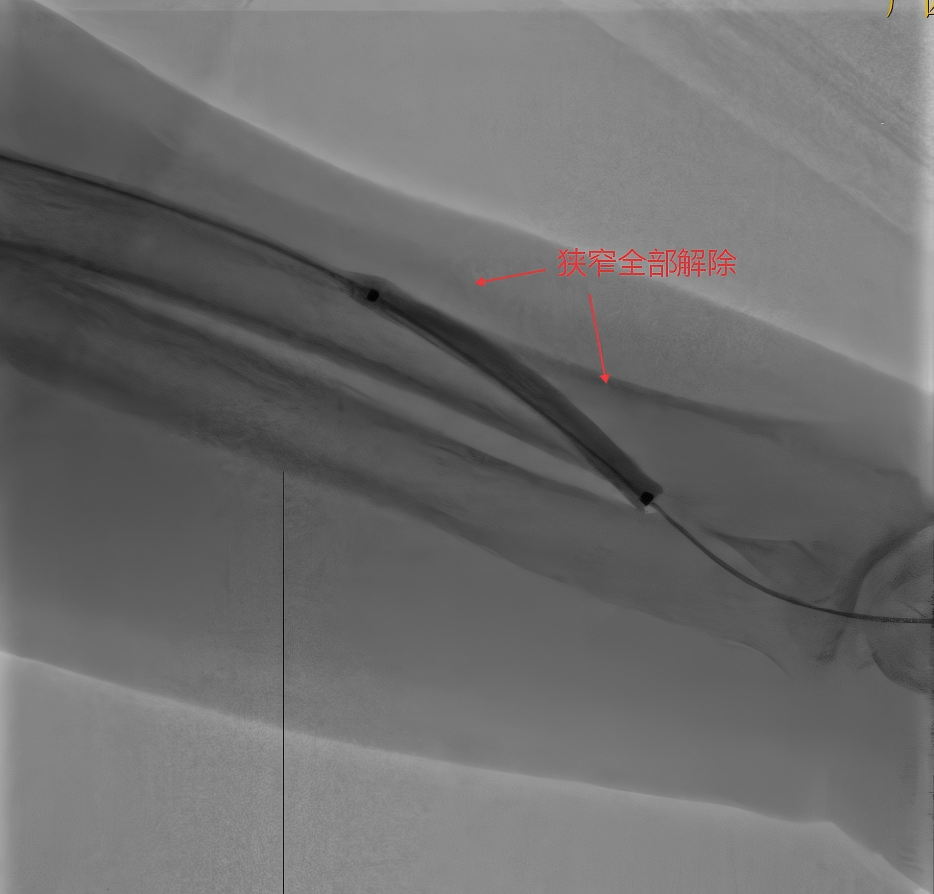

当小心翼翼地用球囊一点点打通,一点点解除狭窄,最后造影的那一刻,所有人都笑了:内瘘通了!血流恢复了!没有血管破裂,没有渗血,一切都比预想的还要好!

术后,当医护人员再次摸到了内瘘处清晰的震颤,听到了有力的杂音,术后1月随访,患者内瘘震颤杂音良好!